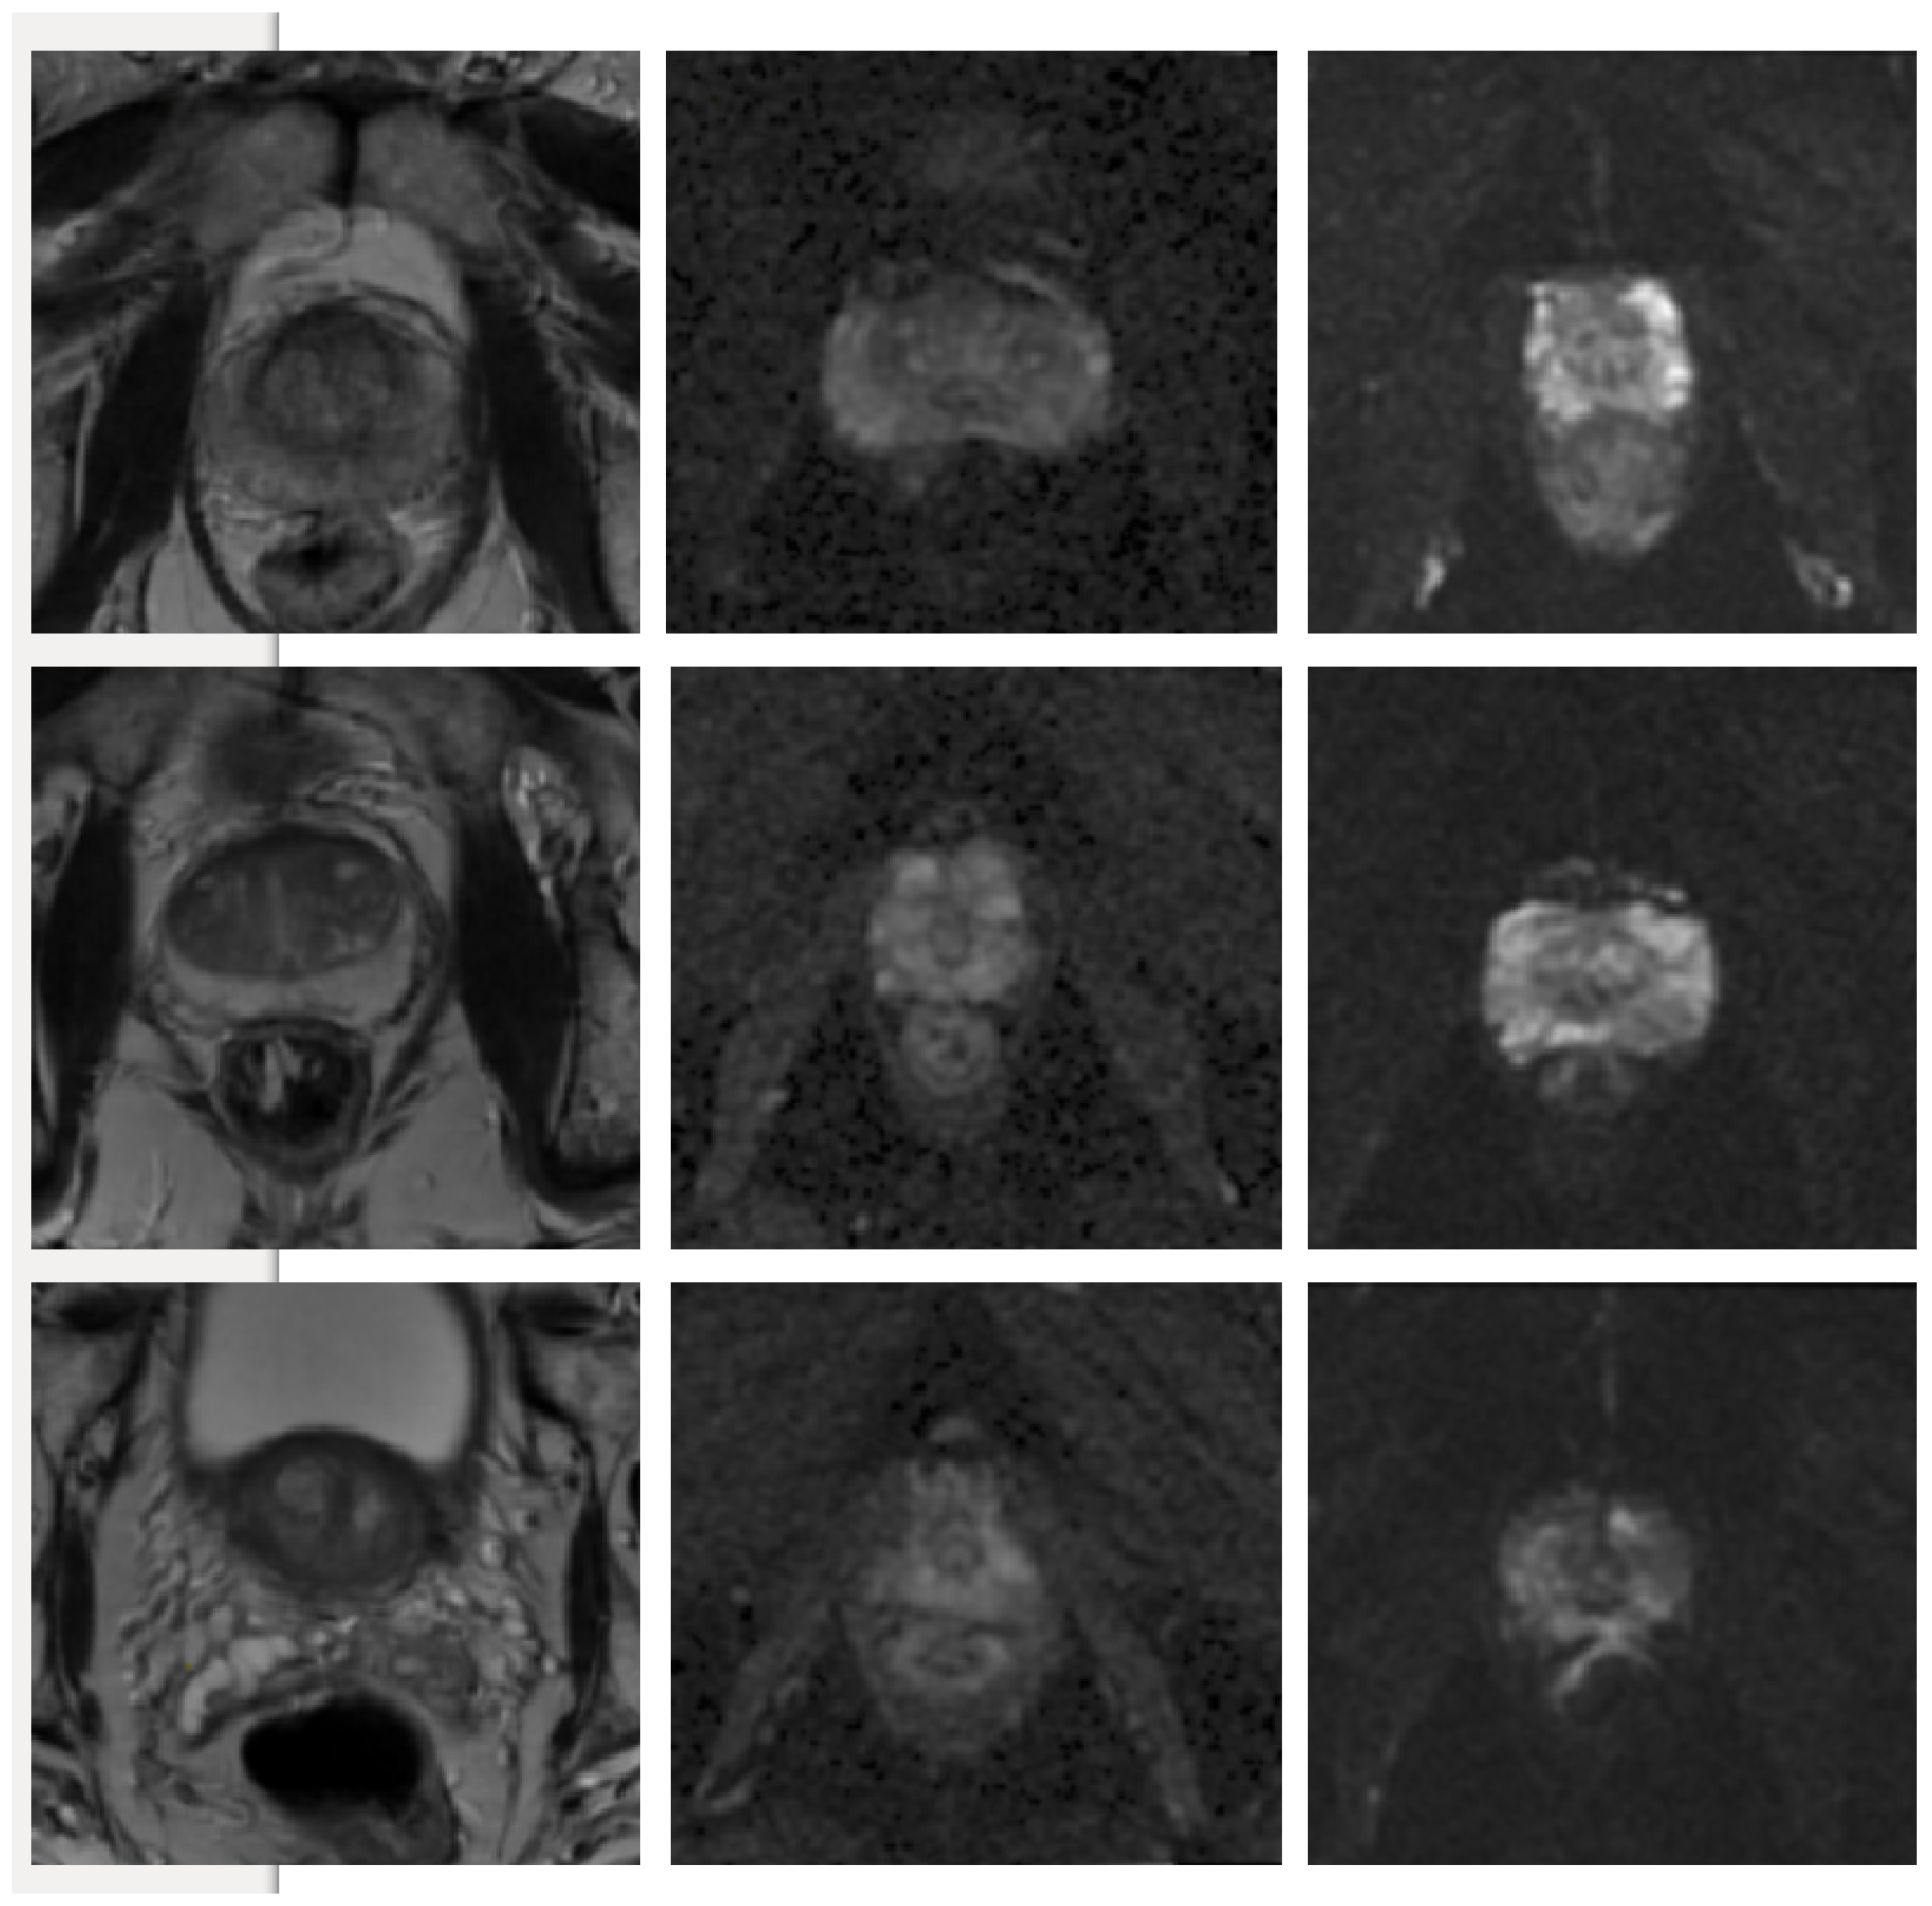

Figure 5.

Visual representation of the predicted segmentation for each model and each modality for a single slice from a case study. From the top row to the bottom: T2W, ADC and DWI. From left to right: Raw test image, Ground truth boundaries in green, U-Net’s prediction in purple, cGAN’s prediction in blue and cycleGAN prediction in red. The quantitative results show the best performance for cGAN followed by U-Net for all evaluation metrics. Scaled images are shown in Figure A1 for better visualisation.

Figure A1.

Visual representation of the predicted segmentation for each model and each modality for a single slice from a case study, where the prostate region is zoomed in and the image brightness is increased. From the top row to the bottom: T2W, ADC and DWI. From left to right: Raw test image, Ground truth boundaries in green, U-Net’s prediction in purple, cGAN’s prediction in blue and cycleGAN prediction in red. The quantitative results show the best performance for cGAN followed by U-Net for all evaluation metrics.